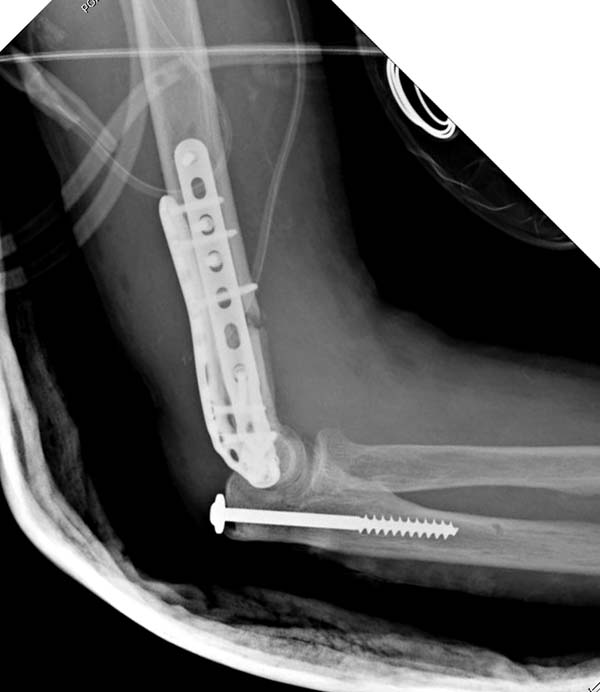

Примеры: первому более 15 лет фиксирован шурупом и tension band

technique, а второй перелом открытый больной 80 лет, после наружного

фиксатора в первом этапе и окончательная фиксация вторично. Третьий раз

внесуставная остеотомия...

Имя     : 1-1 old humerus distal.jpg

Тип     : image/jpeg

Размер  : 50262 байтов

Описание: отсутствует

Url     : http://weborto.net:8080/pipermail/ortho/attachments/20130604/c45a379f/attachment-0019.jpg